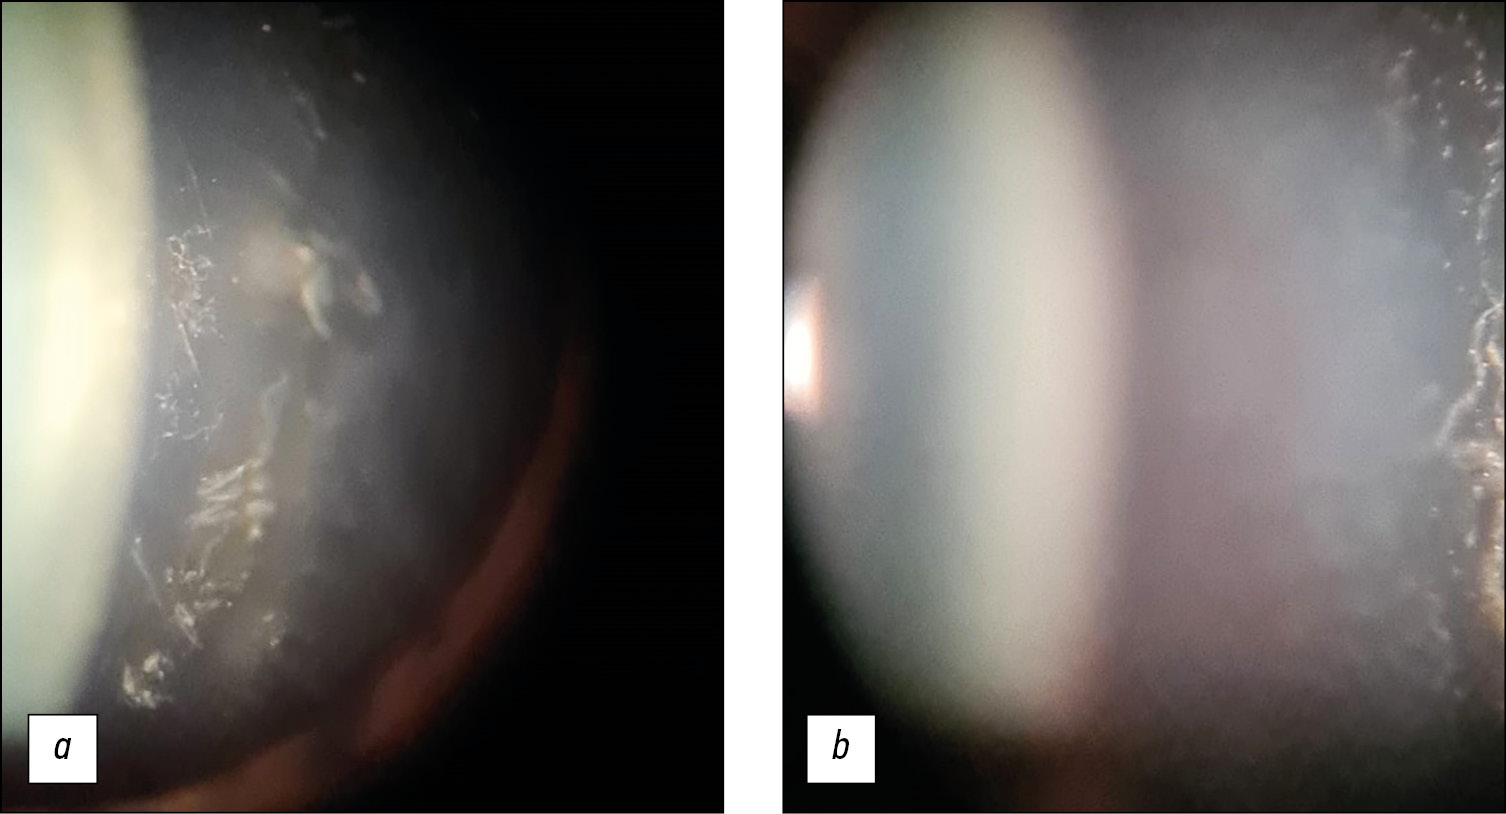

Спустя 7 месяцев от начала заболевания при поступлении в отделение инфекционных и аллергических заболеваний глаз НМИЦ глазных болезней им. Гельмгольца у больного наблюдалась острота зрения OS=0,05; sph (-) 3,25Д=0,9, далее не коррегирует. На правом глазу (OS) на 4–5 часах на склере в области проекции цилиарного тела имеется локальный проминирующий отёк и гиперемия бульбарной конъюнктивы с фиолетовым оттенком, инфильтрат 4 мм в диаметре (рис. 1, а, b).

Рис. 1. Склерит передний узелковый хронический после 7 месяцев лечения: а — локальный проминирующий отёк, узелковый инфильтрат 4 мм в диаметре; b — гиперемия бульбарной конъюнктивы с фиолетовым оттенком.